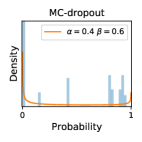

To model how different classifiers will respond to a given input , we assume that the prediction from classifier is sampled from a beta distribution that is characterized by two parameters by and . We further assume that is fixed to the same constant value for all ’s. Under this assumption, each input can be described by ( can be calculated since is fixed), easing further analysis. The Severity Level (SL) of the case represented by image can be characterized by the parameter . The larger the value of , the more severe the case of is. When and are close, the case is ambiguous as the distribution shifts towards being symmetric (i.e. signifying much disagreement among classifiers) rather than being one-sided (i.e. consensus among classifiers that is negative or positive). We provide a set of examples in Figure 2 and also Figure S.8 in the supplementary materials showing how the beta distribution can be used to capture diverse predictions given by an ensemble learner.

In contrast, the MC-dropout method showed the worst overall performance among the three, as it can be seen from the high ratios of SL0 examples among the uncertain negatives in Figure 4. The histograms in Figure 2 provides another perspective to look into the phenomenon, where a decent proportion of MC-dropout model’s predictions on SL0 inputs entailed low confidence (far from 0 or 1), which from another angle explained why MC-dropout was less specific in terms of lower FNP; many no-DR inputs (i.e. SL0) were erroneously assigned high uncertainty by MC-dropout models.

It is still an open question why the evaluated MC-dropout networks signaled relatively high uncertainty on SL0 & SL3 & SL4 data that are less likely to be ambiguous. We conjecture that much of the “uncertainty” indicated by disagreement among test-time dropout samples actually reflects the stochastic nature of dropout networks rather than the real decision uncertainty associated with the data. It is worth noting that the MC-dropout model we evaluated was not weak per se; they all achieved above Area Under Curve (AUC) scores on test sets. The weakness of individual test-time samples (which explains their low-confidence predictions on SL0 & SL3 & SL4) might have been hidden when they are aggregated into an ensemble—a well-known advantage of ensemble learning. Our results suggested that the uncertainty information given by implicit ensemble methods such as MC-dropout and TTA might not be as reliable as that from explicit ensemble approaches (e.g., stacking ensembles). Similar findings on MC-dropout can be found in some previous papers [1].